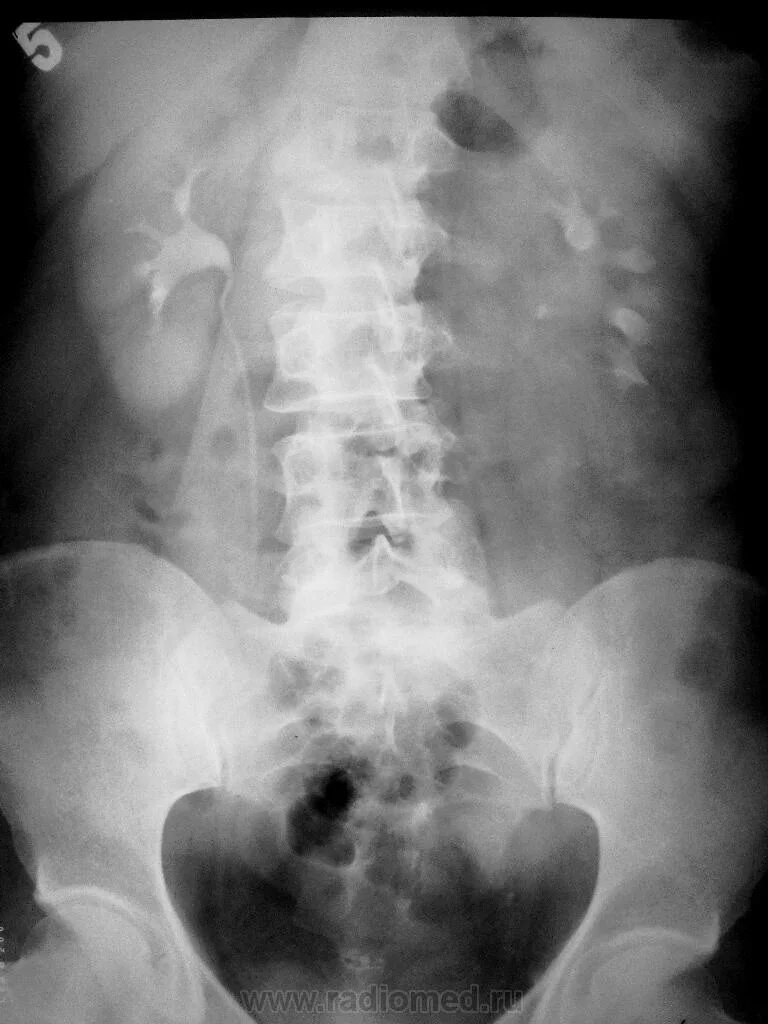

Где сделать урографию